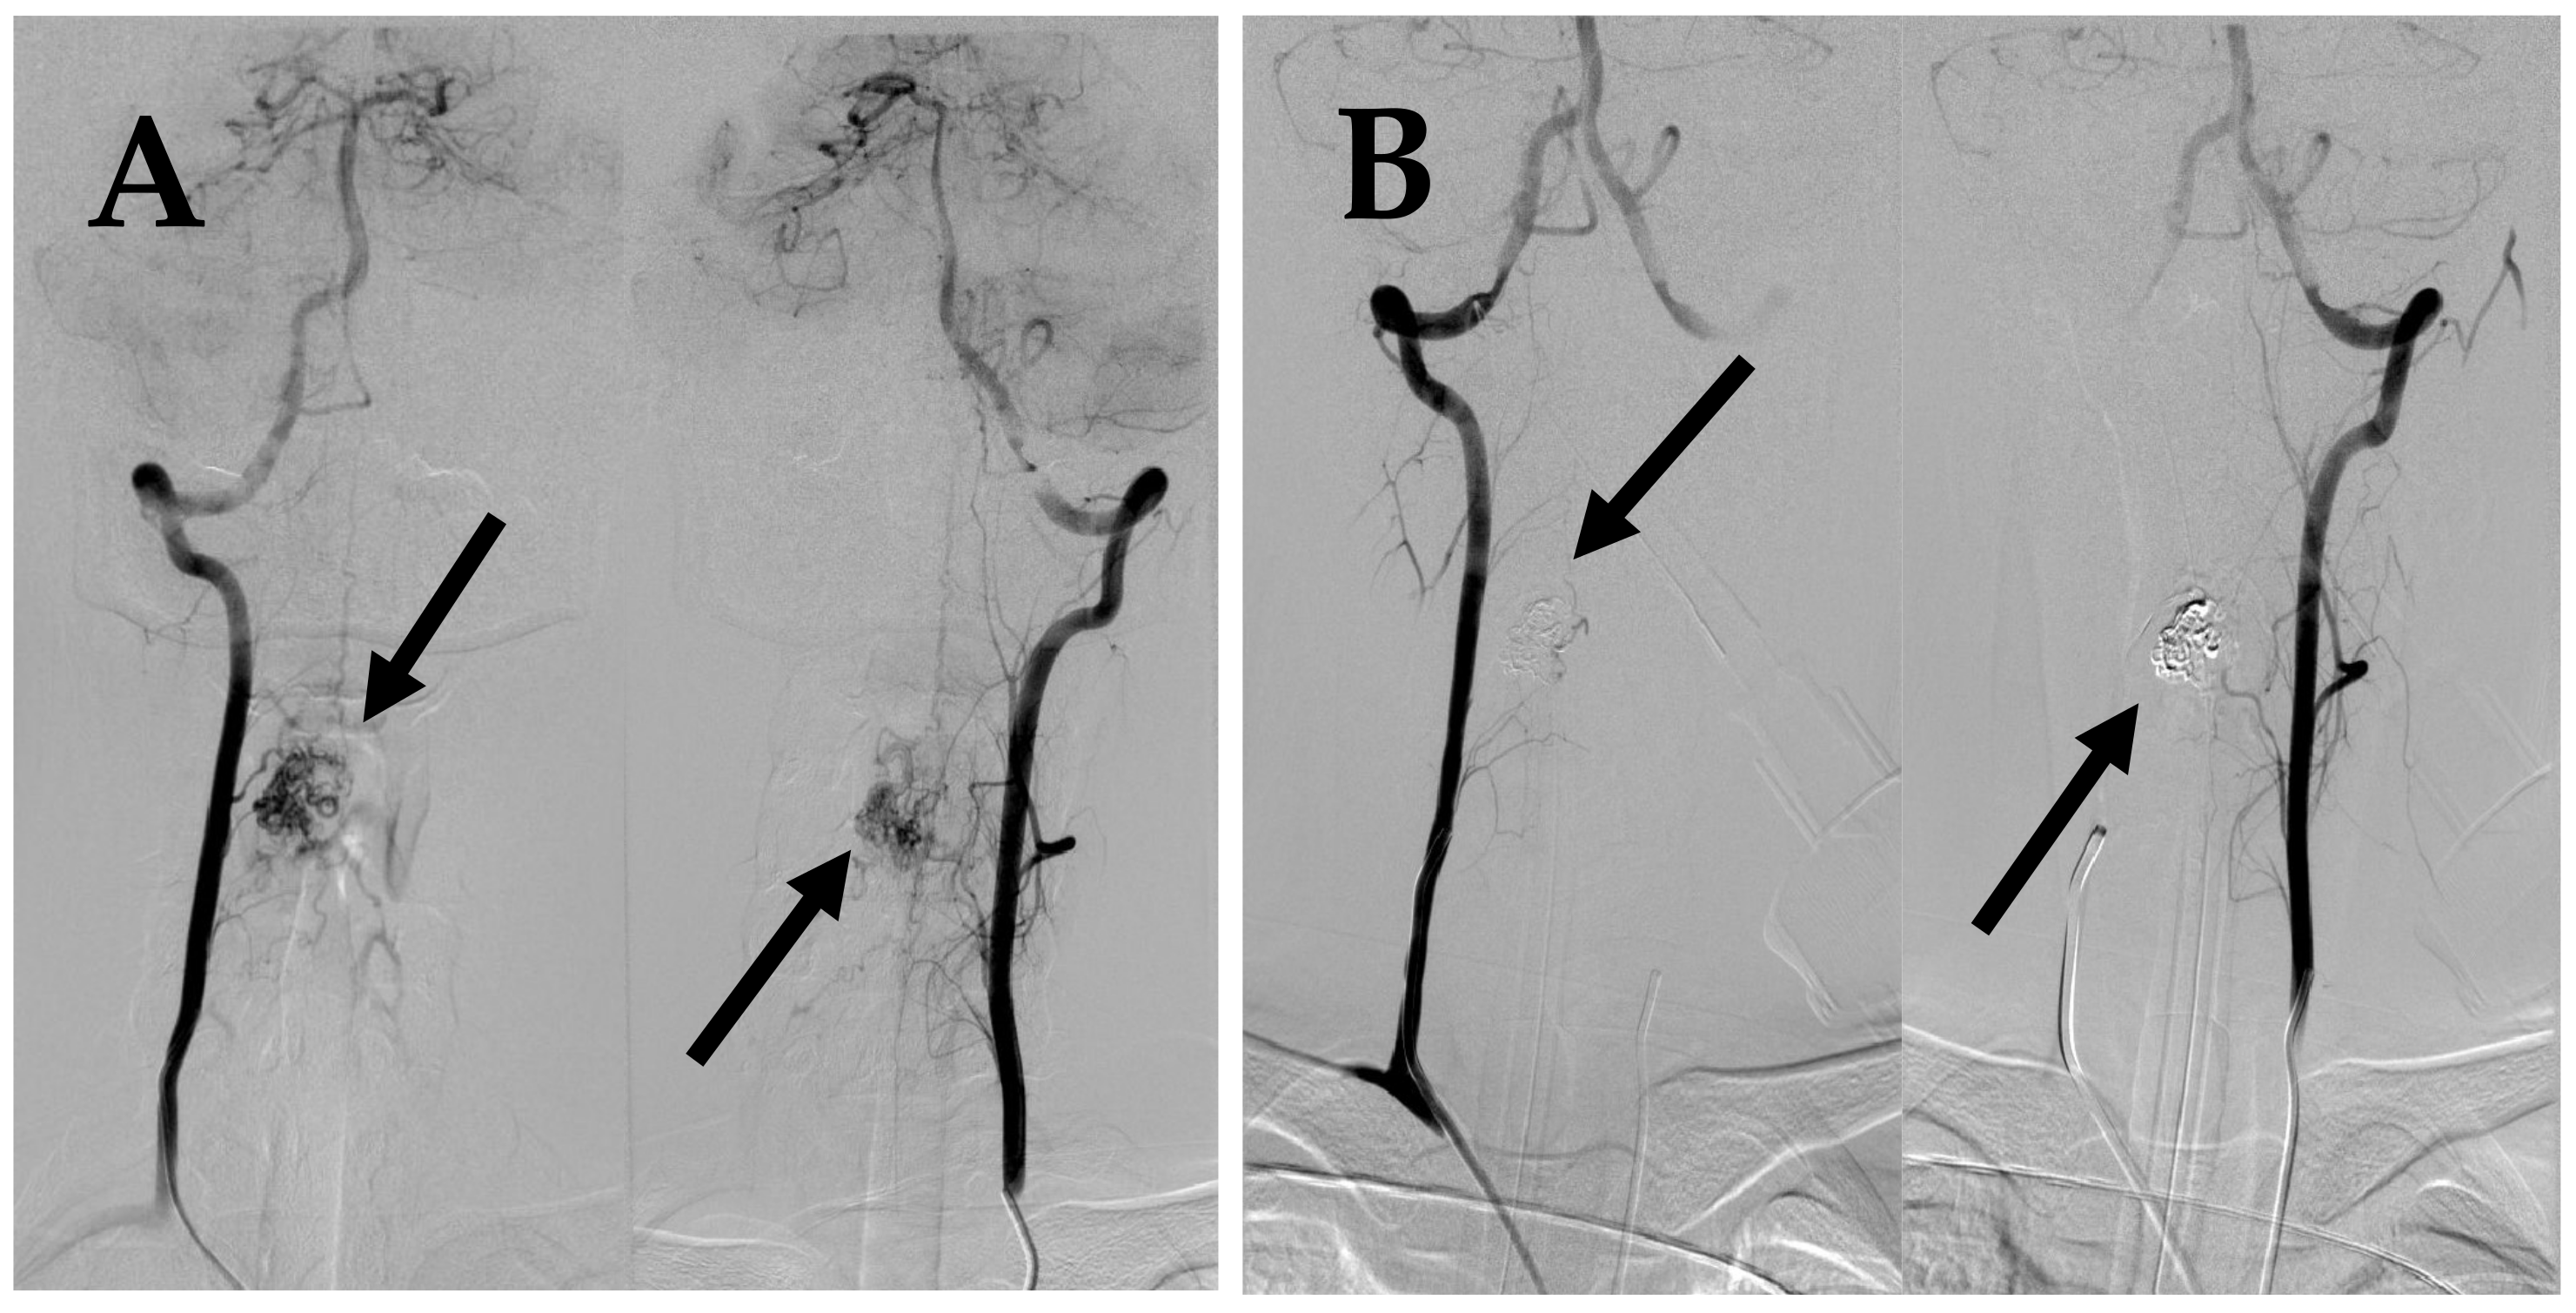

7.2. Second Episode (2020)

7.3. Third Episode (2023)